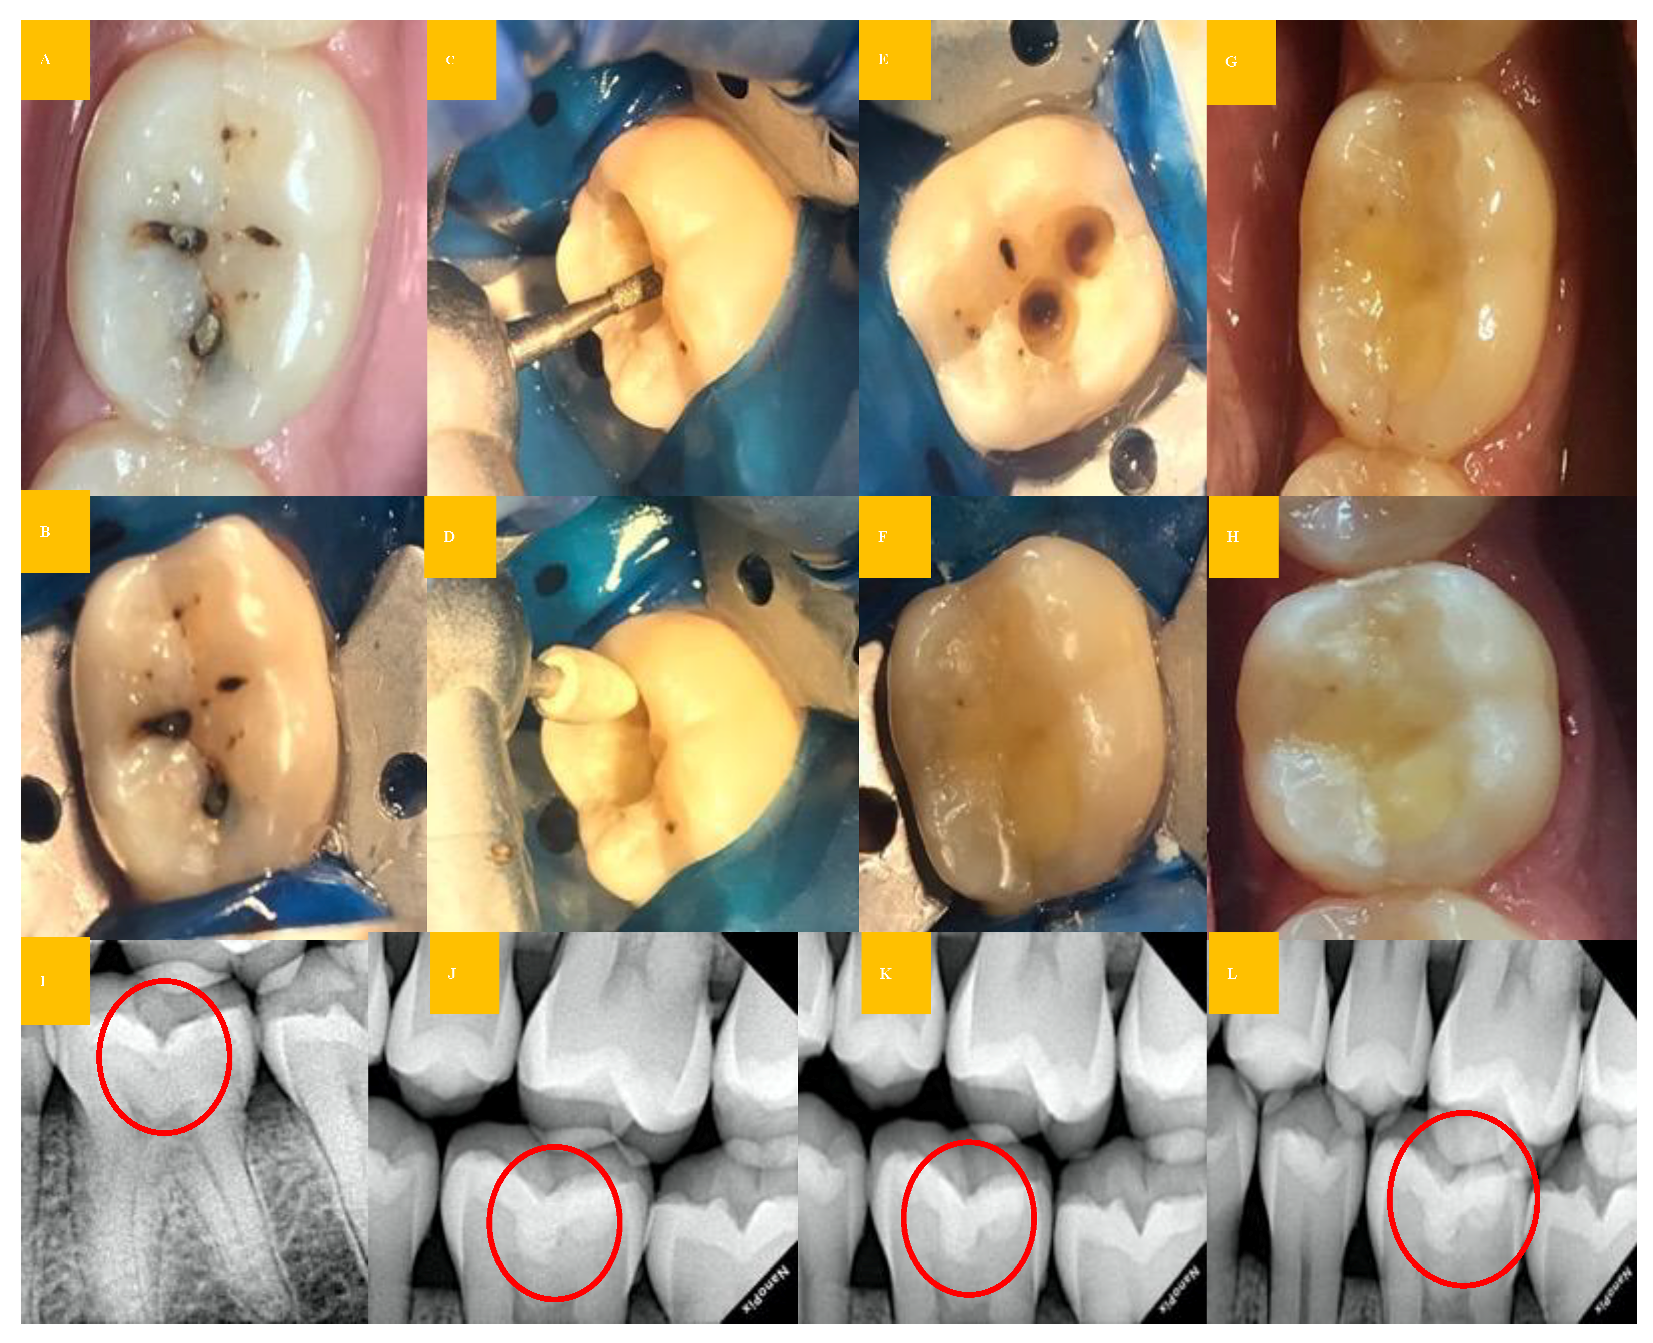

Figure 3 from TREATMENT OF DEEP CARIES LESION AND STEPWISE EXCAVATION Caries Excavation Meaning  Clinical steps for occlusal caries group (bcd group): The aim of this article is to review the scientific evidence for deep caries removal in permanent vital teeth and the choice. Preoperative clinical photo and radiograph (red circle); Since the invention and application of rotary instruments, the operative treatment of carious lesions has often resulted. Two randomized controlled trials comparing stepwise. Caries Excavation Meaning.

Clinical steps for the proximal caries group (BCD group) (A,J Caries Excavation Meaning  Two randomized controlled trials comparing stepwise and complete excavation, while only tangentially relevant to the partial. Since the invention and application of rotary instruments, the operative treatment of carious lesions has often resulted. Preoperative clinical photo and radiograph (red circle); The aim of this article is to review the scientific evidence for deep caries removal in permanent vital teeth and. Caries Excavation Meaning.

Clinical steps for occlusal caries group (BCD group) (A,K Caries Excavation Meaning  Preoperative clinical photo and radiograph (red circle); Clinical steps for occlusal caries group (bcd group): Two randomized controlled trials comparing stepwise and complete excavation, while only tangentially relevant to the partial. The aim of this article is to review the scientific evidence for deep caries removal in permanent vital teeth and the choice. Since the invention and application of rotary. Caries Excavation Meaning.